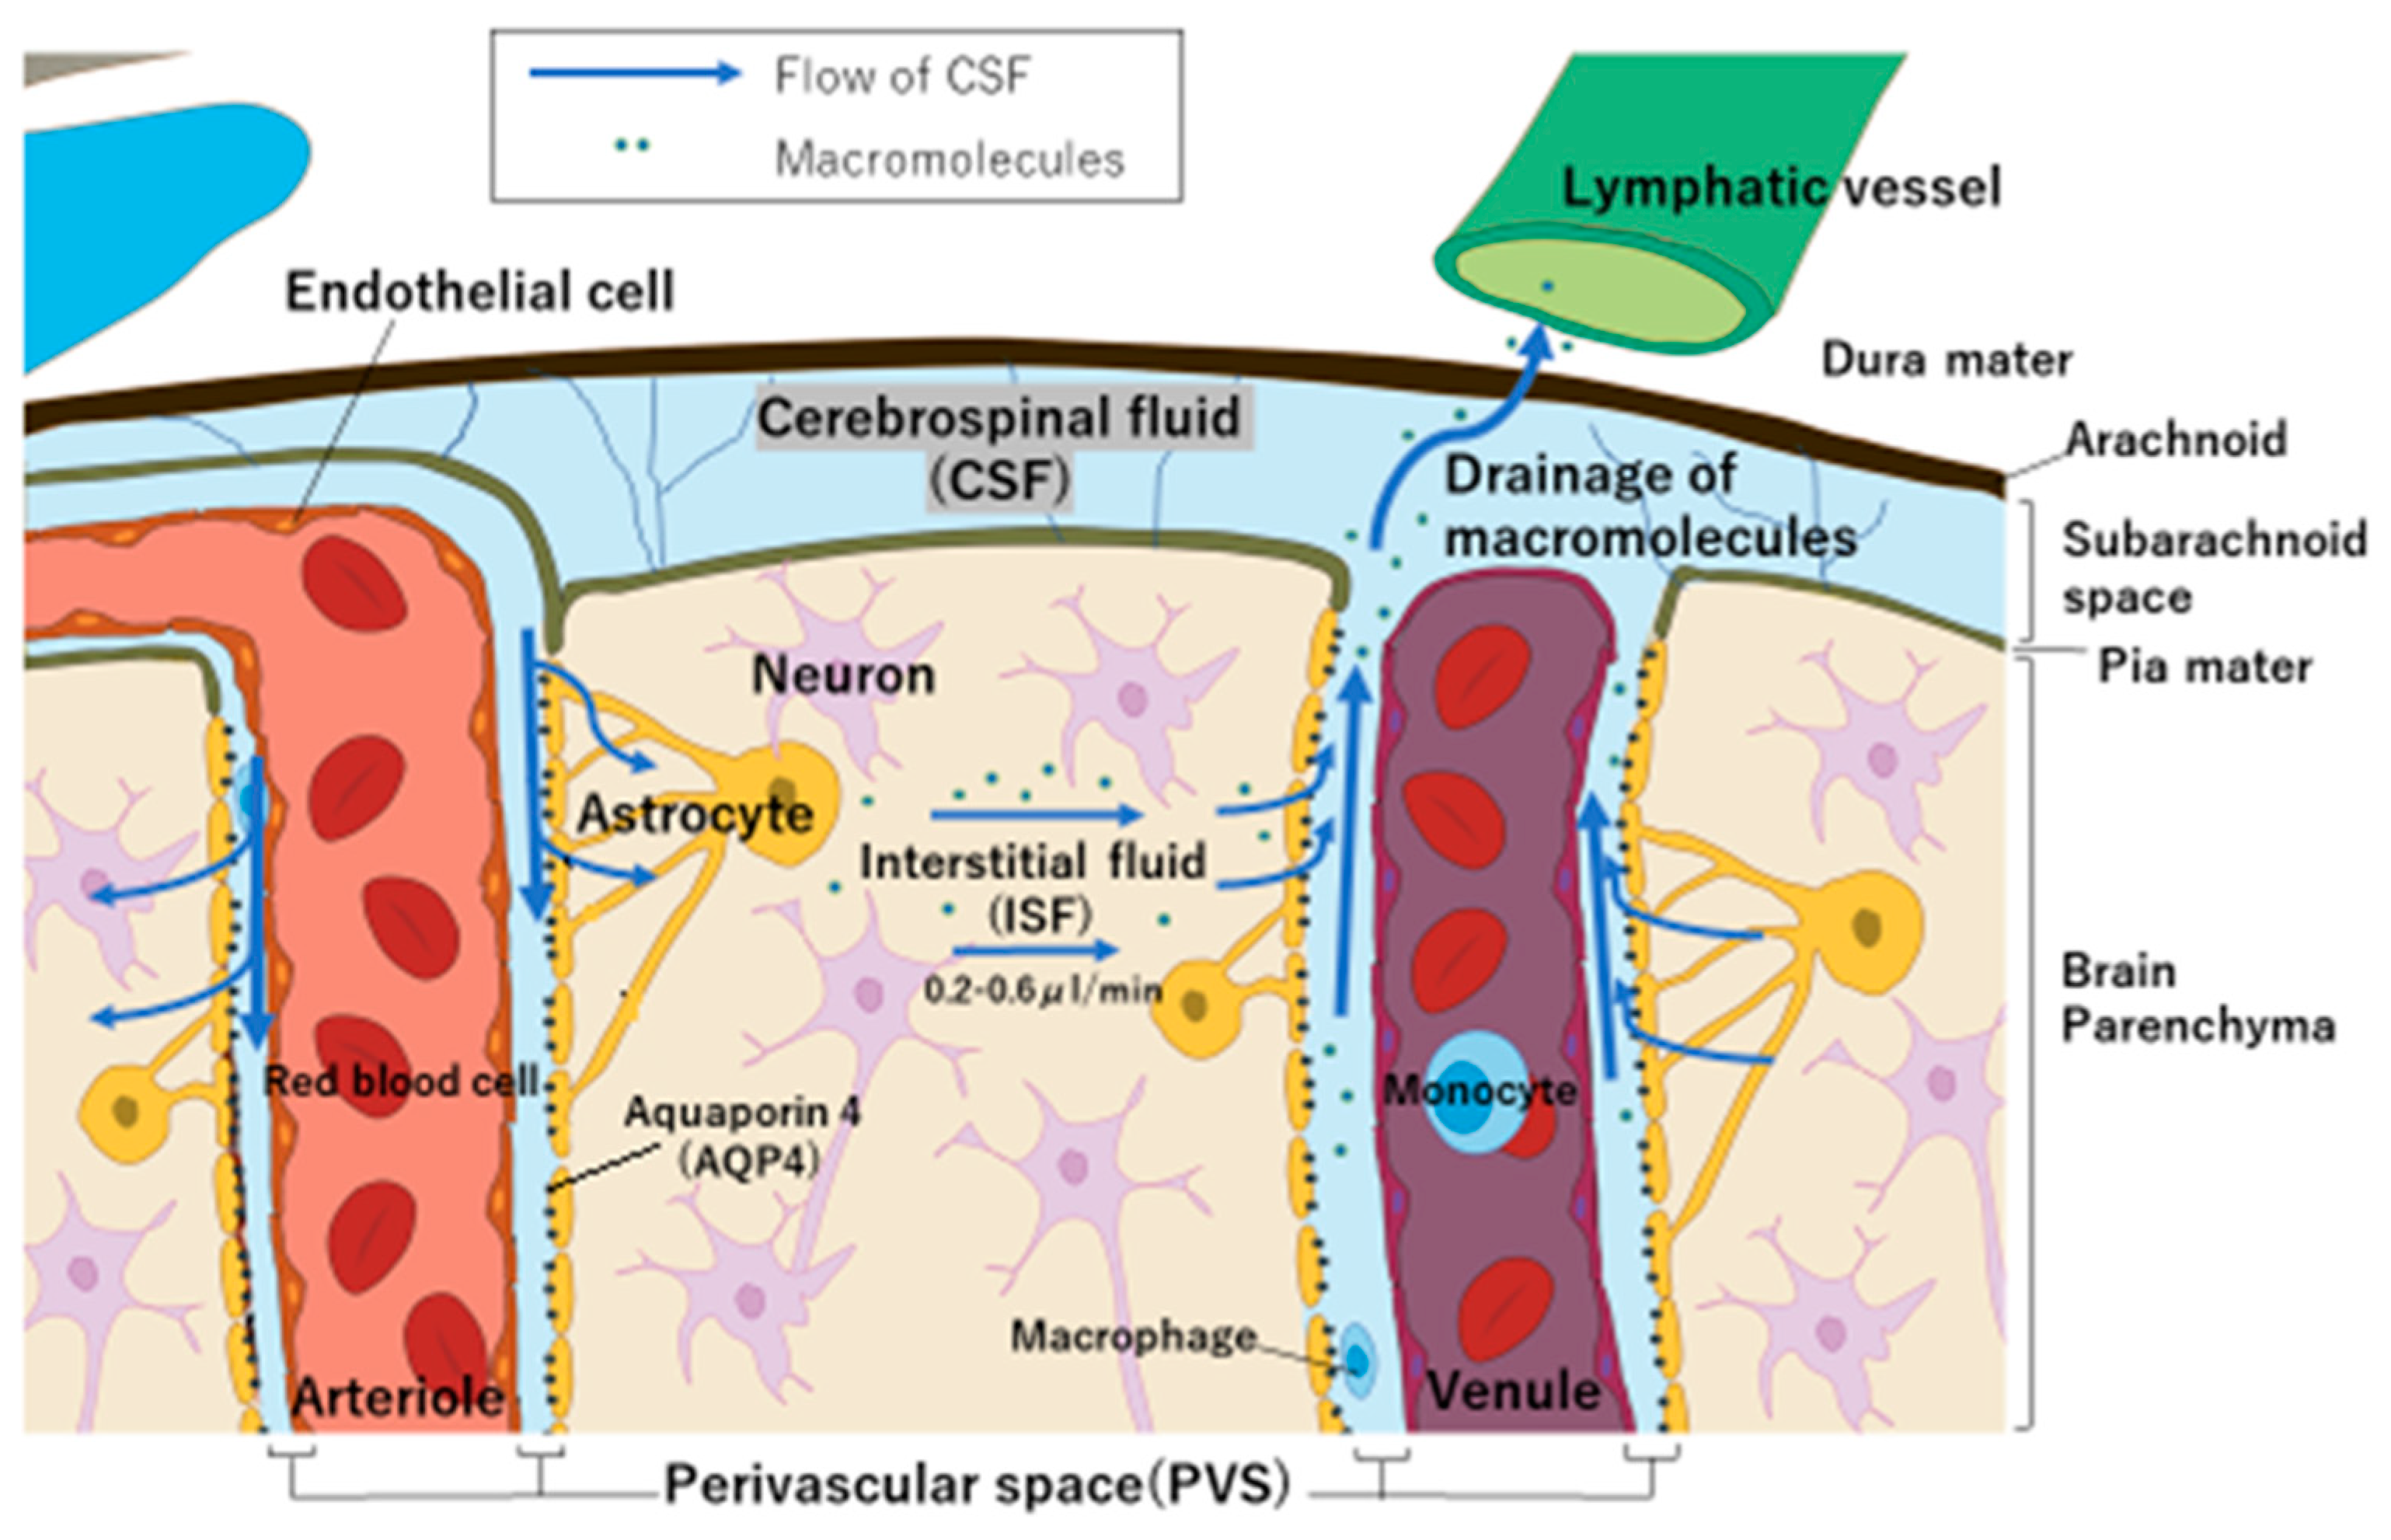

4.1. Why Does BPA Accumulate in Brain Tumors Despite Small Doses of CSF

4.2. Boron Concentration in Normal Tissues and the T/N Ratio in BNCT

4.3. BPA Pharmacokinetics and Pharmacodynamics in Brain Tissue